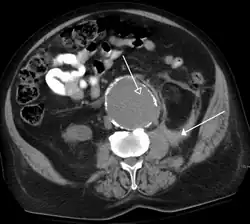

Detection and characterization of renal parenchymal masses is a frequent indication for CT. An initial noncontrast CT is important for detecting calcium or fat in a lesion, and to provide baseline attenuation of any renal masses. Following noncontrast scanning, intravenous contrast is injected and a corticomedullary phase is obtained at approximately 70 seconds (figure 7a, 7b). The corticomedullary phase is characterized by enhancement of the renal cortex as well as the renal vasculature. This phase is valuable in the evaluation of benign renal variants, lymphadenopathy and vasculature, however certain medullary renal masses may not be visible during this phase due to minimal enhancement of the medulla and collecting system. The parenchymal phase is obtained approximately 100–200 seconds after the injection of contrast material (figure 7c). Parenchymal phase imaging demonstrates continued enhancement of the cortex, enhancement of the medulla, and various levels of contrast material in the collecting system. The parenchymal phase is highly important for the detection and characterization of renal masses, parenchymal abnormalities, and the renal collecting system. This method of imaging does not evaluate for abnormalities of the collecting system.

-

FIGURE 7. Selected images from a renal mass specific protocol CT. Corticomedullary phase (axial 7a) demonstrates peripheral enhancement of the renal cortex with minimal opacification of the renal medulla. There is a large renal cell carcinoma in the left kidney (right in image) which can be differentiated from the normal renal parenchyma by the heterogeneous and differential enhancement. The renal artery and vein are opacified in this phase as well. The collecting system is not opacified (coronal reformat 7b). In the parenchymal phase, the renal cortex and the medulla are enhancing. The renal cell carcinoma in the left kidney is not as well defined when compared to the corticomedullary phase images, but is actually slightly more conspicuous. There is some contrast noted within the collecting system during this phase (7c).